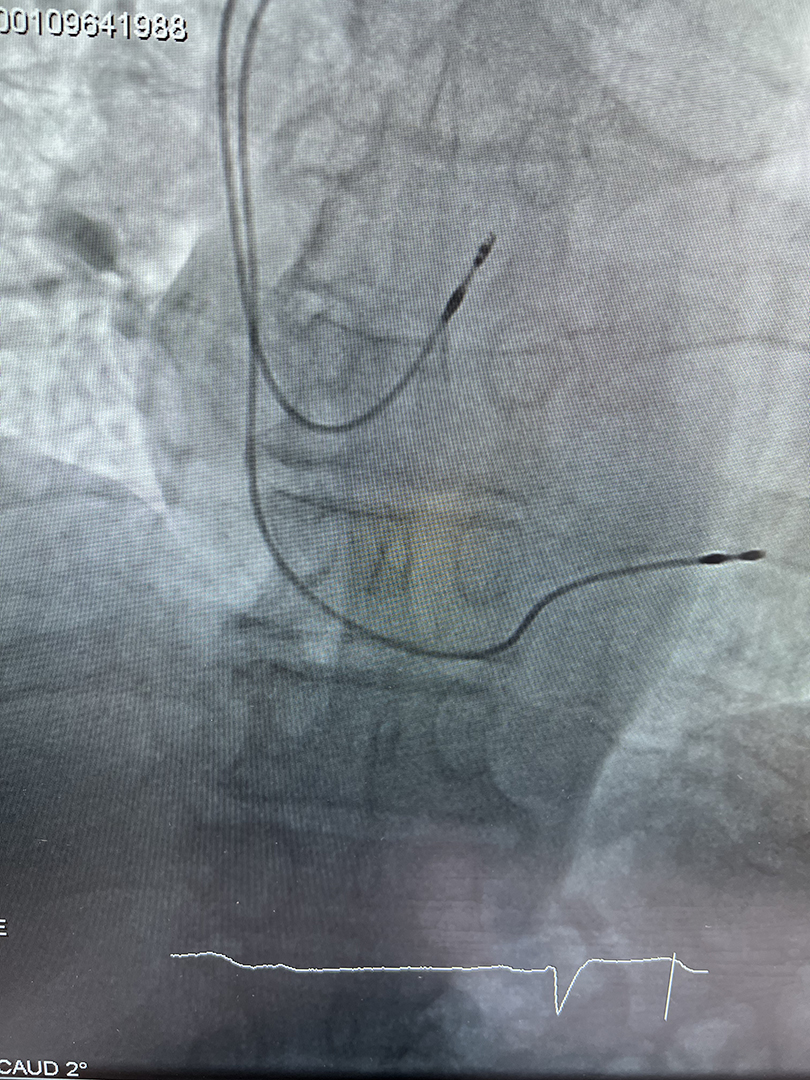

Операция по установке ЭКС проводится в операционной отделения ангиографии, используется местная анестезия. В верхней части грудной клетки выполняется небольшой разрез, электроды проводят в камеры сердца через подключичную вену при помощи систем доставки — через интродьюсеры. После того, как конец электрода оказывается в нужном месте, его прикрепляют к стенке сердца при помощи специальной системы фиксации. Собственно кардиостимулятор подшивается к грудной мышце. Для того чтобы убедиться, что кардиостимулятор и электроды расположены правильно, проводится рентгенконтроль. Послеоперационное наблюдение осуществляется в отделении кардиологии.

Электроды подведены к полостям сердца